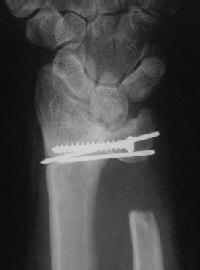

Case 3. Adult bilateral congenital Madelung's deformity with pain and extensor tendinitis, treated with the Sauve Kapandji (Lauenstein) procedure: segmental distal ulnar ostectomy and distal radioulnar joint fusion.

Right side, postop.

And postop: Here, an inadequate ulnar gap led to heterotopic bone formation which almost resulted in a pseudarthrosis.